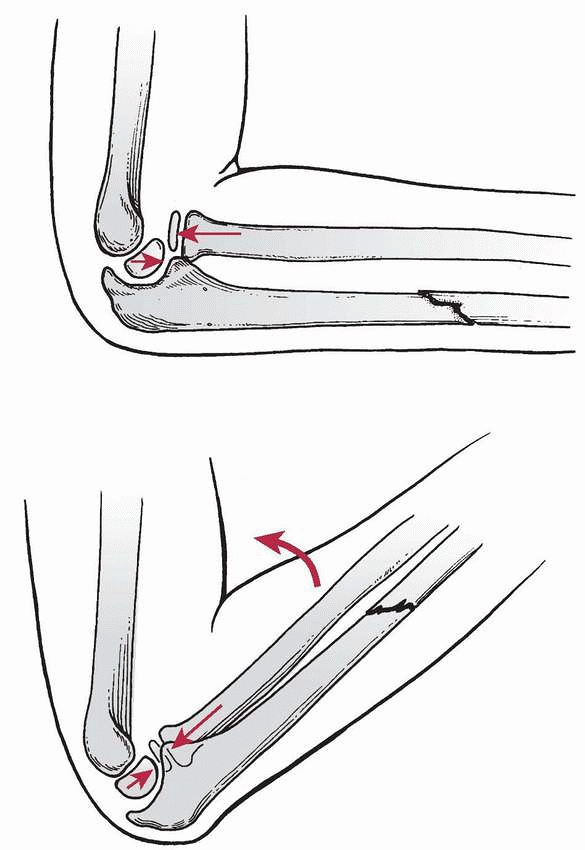

|

FIGURE 12-16 Hyperextension theory. A. Hyperextension: forward momentum caused by a fall on an outstretched hand forces the elbow into extension. B. Radial head dislocation: the biceps contracts, forcibly dislocating the radial head. C. Ulnar fracture: forward momentum causes the ulna to fracture because of tension on the anterior surface.